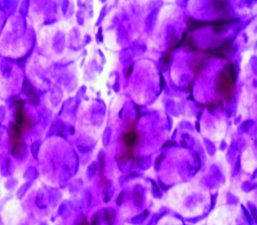

La citología de impresión (Fig. 16) permite identificar los cambios metaplásicos experimentados por la superficie epitelial conjuntival como consecuencia del ojo seco e identificar las características histológicas de las células mucosecretantes y de otras células que conforman a la superficie epitelial conjuntiva.

Figura 16: Citología de impresión

Permite diferenciar cuadros de ojo seco, de alergia, de disfunción de glándula de Meibomio, de toxicidad y realizar un correcto diagnóstico diferencial. Estudios comparativos con biopsia labial de pacientes portadores de Síndrome de Sjögren 22 le dan un gran valor diagnóstico de esa enfermedad.

Es de gran utilidad para diagnosticar disfunciones límbicas.